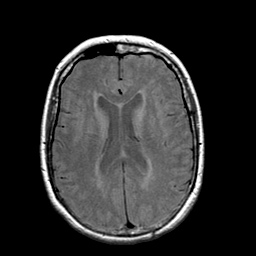

Stroke: proton density-weighted MR #1 -- Slice #15

[Home][Help][Clinical] Slice 15